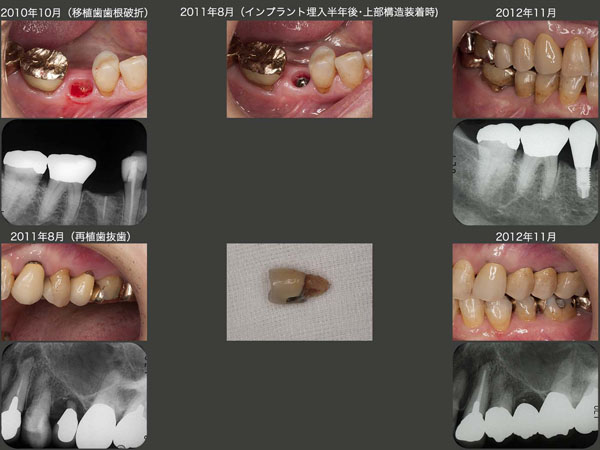

2010年10月に,移植した右下5に歯根破折が生じた.この原因は移植の不手際というよりは,左上5を連結固定しなかったことが一番の原因であると思われる.すなわち左上5に動揺が生じたために左側での咀嚼を避け,結果右下5の荷重負担が増大したと想像できる.もちろん移植した右下5(元は右下1)も右下6と連結固定したほうが咬合力に対応できた.

さて今回の右下5の治療方針は,インプラントを用いることにした.11年2月に埋入手術を行い,8月に上部構造を装着した.一方同月にブラブラになってしまった左上5を抜歯し,こちらは12年4月にブリッジを装着した.なお,スライド右端は,12年11月の状態である.